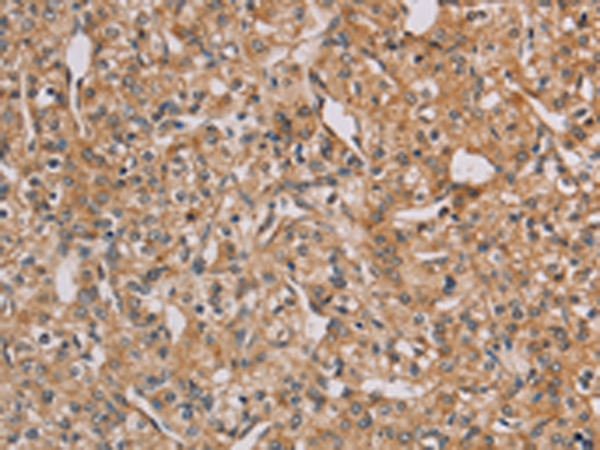

分类: 科研抗体货号: P07473别名: EBN; BFNC; EBN1; NACHR; NACRA4; NACHRA4应用: WB,IHC反应种属: Human